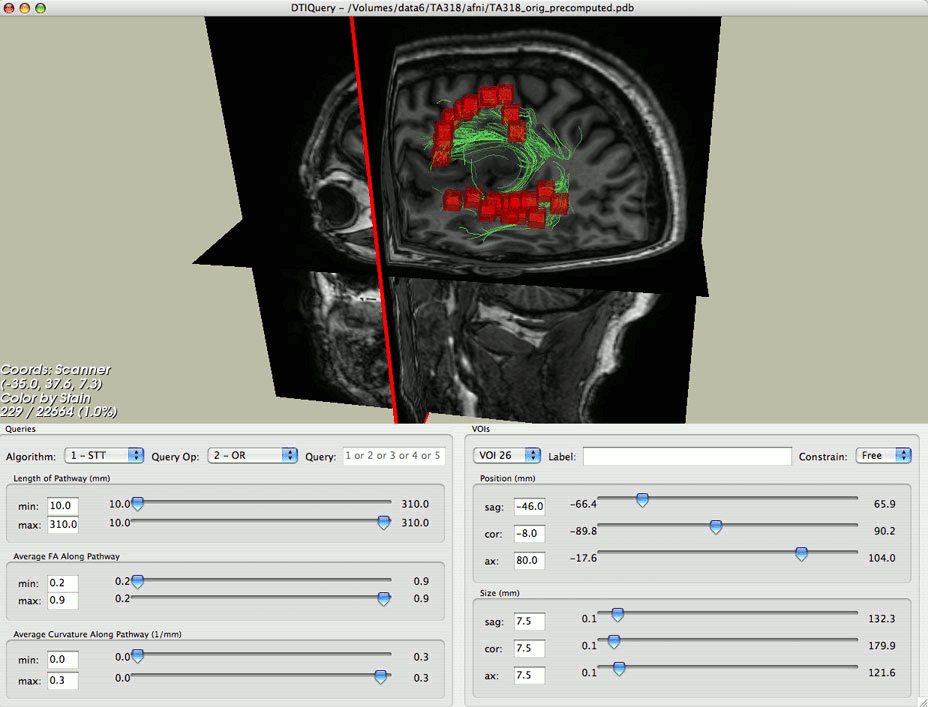

DTIQuery

- Tractography, fODF, tensors

- Fibernavigator

- MRview